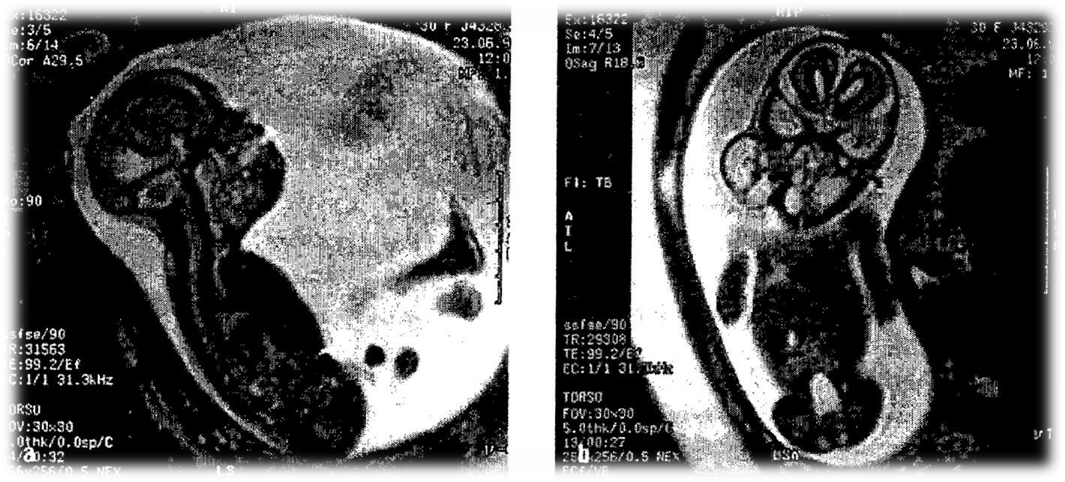

Мал. 11. Діагностика уражень цнс плода. Мрт

Нині в діагностиці пренатальних гіпоксичних уражень ЦНС плода велико­го значення набувають новітні методи медичної візуалізації. Одним із таких методів є метод магнітно-резонансної томографії (МРТ, мал. 11). Після того як було доведено безпеку застосування МРТ для вагітної і пло­да, цей метод набув значного поширення.

Метод дає змогу одержати зображення з найкращим, порівняно з іншими методами, контрастом тканин досліджуваного об'єкта і вивчати зображення об’єкт та в будь-якій заданій проекції. При цьому метод дає можливість точно визначи­ти характер патологічного процесу, його локалізацію, поширеність в організмі.

Використання МРТ в акушерстві значно підвищило точність діагностики природжених вад розвитку плода, патології плаценти, стану навколоплідних вод. ЦНС плода є головною зоною дослідження МРТ в акушерстві. На сьогод­ні не існує інших методів візуалізації, які б давали змогу отримати точніші дані про стан ЦНС плода та вади її розвитку. Специфічність МРТ для діагностики уражень ЦНС плода становить 97 %.